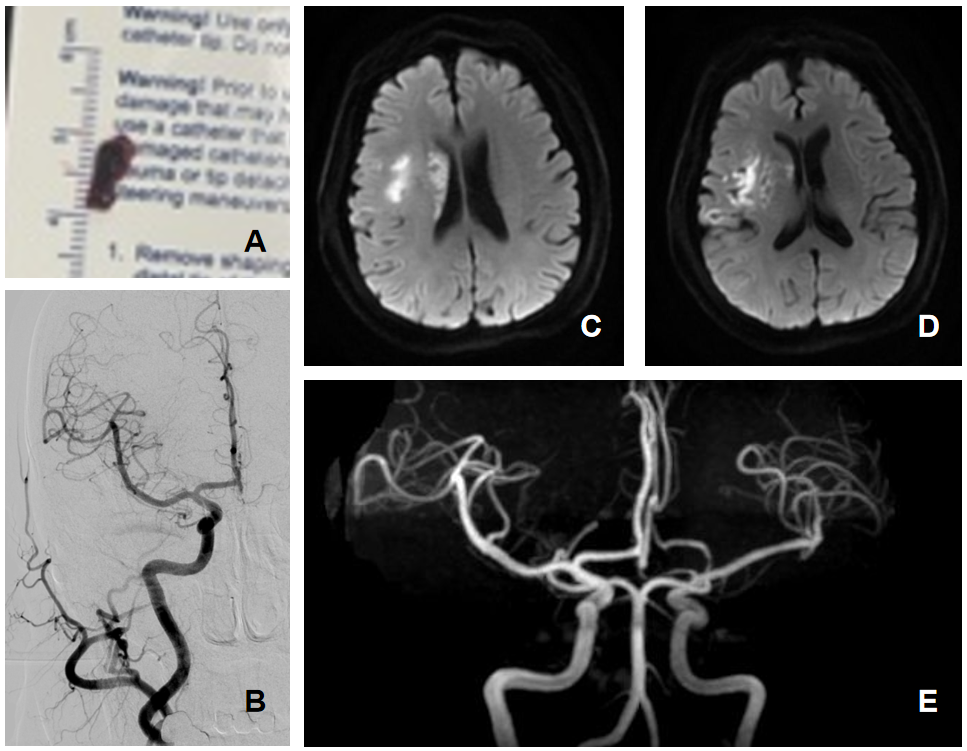

患者及家属同意手术后,王也与神经内科医师沈懿快速为患者建立通路,采用支架取栓联合导管抽栓技术,仅一次抽吸,就取出了约1cm长的大块暗红色血栓,造影显示脑动脉血流即刻恢复,供血通畅(图2A-B),仅用时1小时,杨奶奶受损的肢体肌力明显恢复,说话也流利了不少。

术后,患者被转运至神经内科高危卒中单元,神经内科主治医师杨骊鹏与医师柴英、张思远对患者展开下一步的综合性诊疗和卒中护理,复查显示经过治疗的右侧颈内动脉始终保持通畅(图2C-E)。目前已经顺利渡过急性期,正在积极进行肢体功能康复训练。

(A)经抽吸取栓,取出约1cm长的大块暗红色血栓

(B)复查造影,右侧颈内动脉及大脑中动脉血流完全恢复

(C,D)术后头颅MRI影像提示右侧颈内动脉供血区多发局限性梗死病灶

(E)术后复查血管影像,右侧颈内动脉及大脑中动脉通畅,显影良好